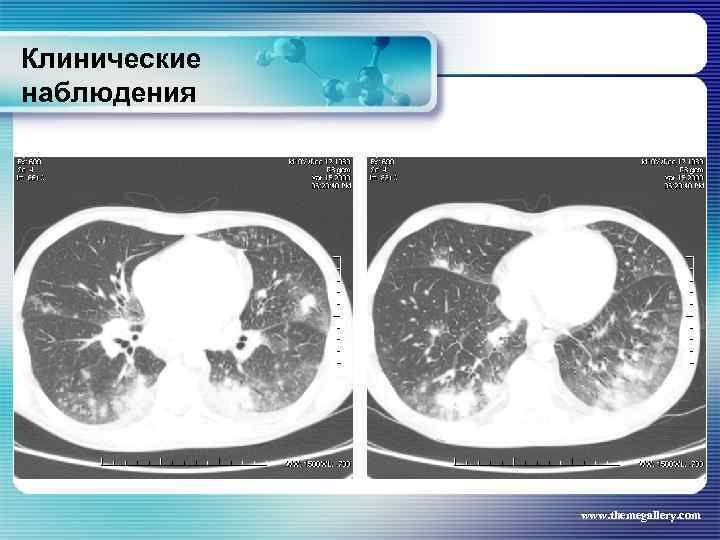

Клинические наблюдения Тот же пациент Был сформулирован клинический диагноз: Лифома Ходжкина, нодулярный склероз IV B стадия с поражением шейных, надключичных, подчелюстных, подмышечных, переднегрудных, парастернальных, паховых, внутригрудных, абдоминальных лимфатических узлов, печени, костного мозга, позвонков. В связи с выраженной нарастающей интоксикацией была начата терапия преднизолоном и первый цикл ВЕАСОРР. на этом фоне появились: резко повышенные показатели трансаминаз, асцит, массивные белковые отёки, сохранилась опухолевая интоксикация. Развилась аплазия гемопоеза. Доза преднизолона была увеличена. На этом фоне развилась полисегментарная грибковая пневмония. www. themegallery. com

Клинические наблюдения Тот же пациент Был сформулирован клинический диагноз: Лифома Ходжкина, нодулярный склероз IV B стадия с поражением шейных, надключичных, подчелюстных, подмышечных, переднегрудных, парастернальных, паховых, внутригрудных, абдоминальных лимфатических узлов, печени, костного мозга, позвонков. В связи с выраженной нарастающей интоксикацией была начата терапия преднизолоном и первый цикл ВЕАСОРР. на этом фоне появились: резко повышенные показатели трансаминаз, асцит, массивные белковые отёки, сохранилась опухолевая интоксикация. Развилась аплазия гемопоеза. Доза преднизолона была увеличена. На этом фоне развилась полисегментарная грибковая пневмония. www. themegallery. com